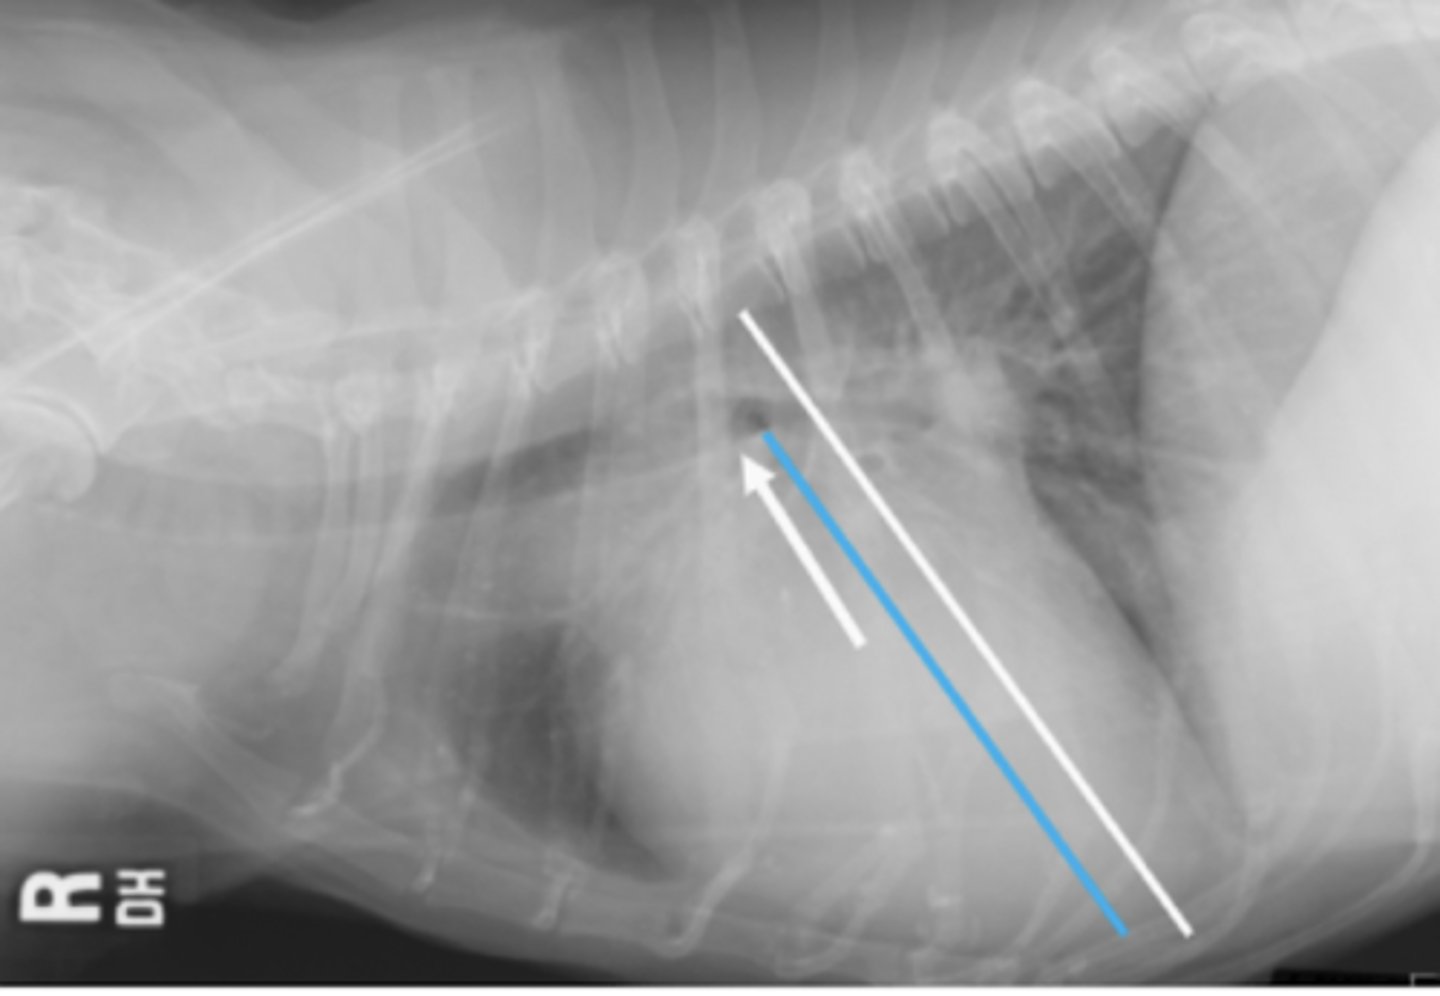

megaesófago

patología:

megaesófago, por cuerpo extraño

neumonía por aspiración por

la parenquíma pulmonar, por riesgo de neumonía por aspiración

si vemos megaesófago en una radiografía, es importante evaluar: